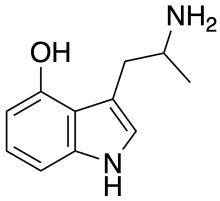

5-HO-αMT (αMS/α-methyl-5-HT) | 3-(2-aminopropyl)-1H-indol-5-ol | 304-52-9 |

α-Alkyltryptamines are a group of substituted tryptamines which possess an alkyl group, such as a methyl or ethyl group, attached at the alpha carbon, and in most cases no substitution on the amine nitrogen.[17][18][19] α-Alkylation of tryptamine makes it much more metabolically stable and resistant to degradation by monoamine oxidase, resulting in increased potency and greatly lengthened half-life.[19] This is analogous to α-methylation of phenethylamine into amphetamine.[19]

Many α-alkyltryptamines are drugs, acting as monoamine releasing agents, non-selective serotonin receptor agonists, and/or monoamine oxidase inhibitors,[20][21][22][23] and produce psychostimulant, entactogen, and/or psychedelic effects.[17][18][19] The most well-known of these agents are α-methyltryptamine (αMT) and α-ethyltryptamine (αET), both of which were used clinically as antidepressants for a brief period of time in the past and are abused as recreational drugs.[18][19] In accordance with its action as a dual releasing agent of serotonin and dopamine, αET has been found to produce serotonergic neurotoxicity similarly to amphetamines like MDMA and PCA, and the same is also likely to hold true for other serotonin and dopamine-releasing α-alkyltryptamines such as αMT, 5-MeO-αMT, and various others.[24]